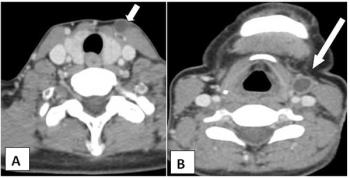

Case History: 24-year-old male with complaints of shoulder pain, slowly increasing swelling for five years.